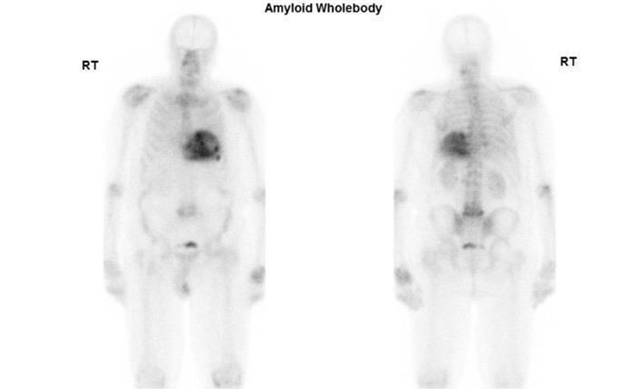

Other radiopharmaceuticals MDP

Other traces of bone scintigraphy are still under investigation and have very low sensitivity for CA. 99m TC-MDP (99mTc-methylene diphosphonate) is also a very common bone scan tracer. However, the reported sensitivity of the tracer is very low.54 Other studies stated that The tracers 99mTc-MDP and 99mTc-aprotinin are not recommended for this purpose.55

The last case we present here is a recently published for incidentally detected cardiac amyloidosis on 99mTc-MDP bone scintigraphy. An 86-year-old man with prostate cancer treated several years ago presented with elevated prostate-specific antigen and back pain with a known history of hypertension, hyperlipidemia, and heart failure with preserved ejection fraction (HFpEF). A 99mTc-MDP scan was indicated to rule out bone metastasis. The scan findings were negative for metastatic disease. However, degenerative changes in multiple joints were noted, and the tracer's unexpected mild, diffuse myocardial uptake was further investigated by performing 99mTc-PYP for suspected CA. The PYP scintigraphy demonstrated intense myocardial uptake in both planar and SPECT. Histologically, by Serum immunofixation, AL was ruled out, confirming the uptake was consistent with ATTR CA. The patient was referred to the cardiology department for further treatment (Figure 9).56 In another small cohort study of 19 biopsy-proven patients who underwent DPD and MDP scans. In whom MDP showed a mild cardiac uptake 0-1by the Perugini method, DPD demonstrated positive for the patients diagnosed with ATTR.54 (Figure 12)

Figure 12 Demonstrating results of DPD and MDP bone scan in 19 patients undergoing cardiac amyloid study showing no cardiac uptake in MDP where as DPD is positive in most cases. Published by F. Javier, 2012.53